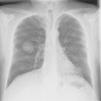

We present the case of a 49-year-old man with no personal history of interest who smoked 80 cigarettes and drank 60g of alcohol per day. He visited the emergency department with sudden-onset cyanosis on the first 3 fingers of the left hand that was preceded by cutaneous pallor with paresthesia and intense pain (Figure 1). He had no other symptoms that were indicative of systemic disease, and the remainder of the physical examination was unremarkable. His heartbeat was regular, with no murmurs, and the distal pulses were palpable and symmetrical in all 4 extremities. The coagulation study was normal, except for D-dimer, which was >5000ng/mL. Prothrombin time and activated partial prothrombin time were normal. Arterial Doppler ultrasound showed that the blood supply reached the spaces between the fingers of the affected hand. Arteriography revealed a distal occlusion of the radial artery of the second finger, with proximal occlusion of the palmar digital arteries of the second and third fingers. The chest x-ray revealed a 4-cm mass on the right lower lobe (Figure 2). Fine needle aspiration findings were consistent with giant cell carcinoma of the lung. The extension study revealed no lymph node involvement. Initial treatment was with low-molecular-weight heparin, which led to a slight improvement in the skin symptoms. Therefore, pentoxifylline, acetylsalicylic acid, and intravenous alprostadil were added sequentially, although the results were mediocre. A clear clinical improvement was observed once the tumor was removed, and the Raynaud phenomenon resolved.